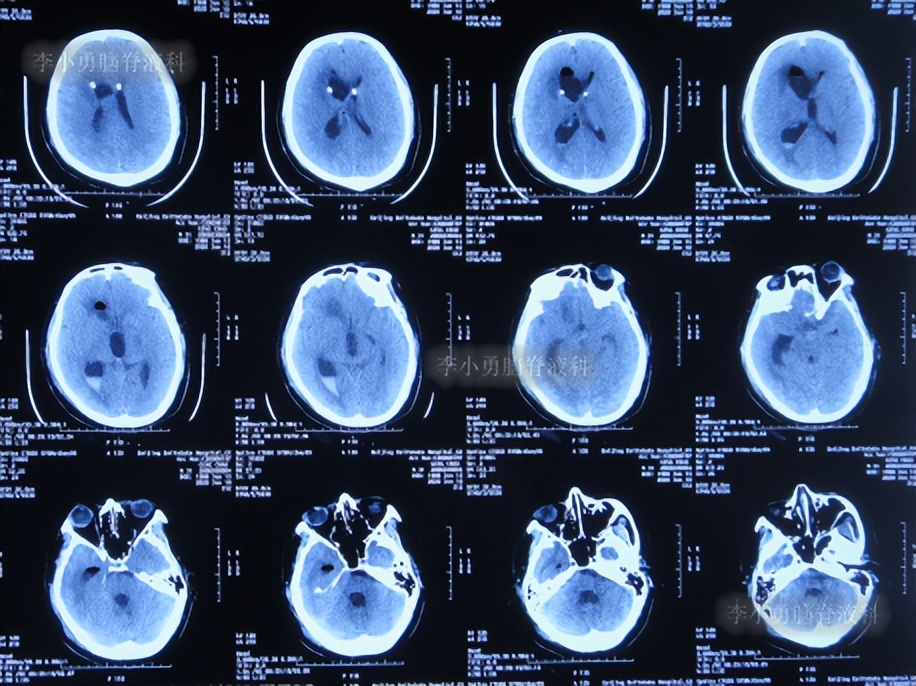

第4次出院后2个月时间内,期间曾4次查头颅影像均示脑室有进一步扩张(图-12、图-13、图-14、图-15),且患者精神逐渐变差。

图-12:2020年3月14日头颅CT

图-13:2020年3月31日头颅核磁

图-14:2020年4月18日头颅CT

图-15:2020年5月9日头颅核磁

第5次住院治疗

第4次出院后2个半月即2020年5月14日,患者意识变差,且不能下地活动,第5次就诊于给予手术的医院,查头颅CT示脑室扩张加重(图-16)。

图-16:2020年5月14日头颅CT